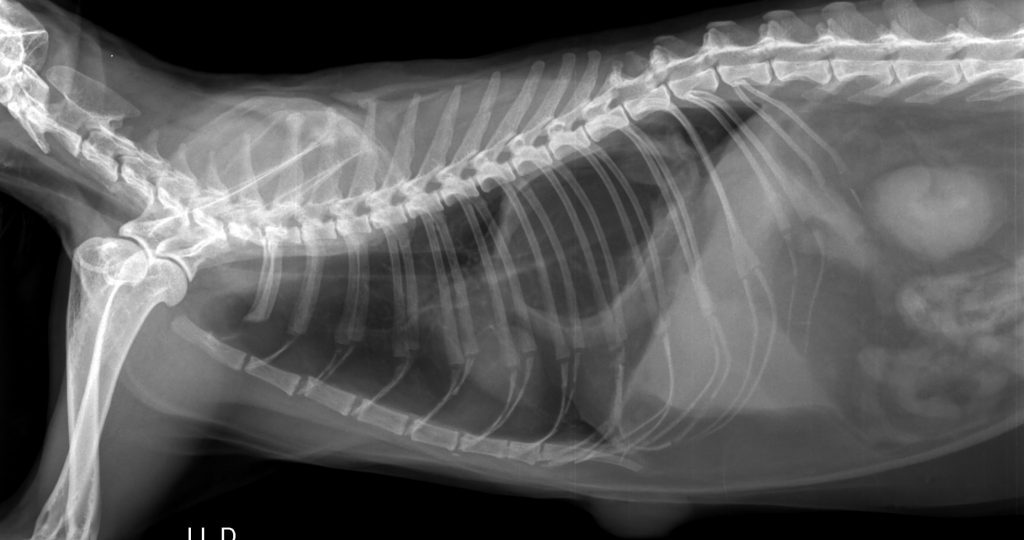

Paciente felino de 12 años con distress respiratorio severo peragudo, cianosis leve. Se presenta un abultamiento de pared corporal ventral a la altura de VIII esternebra.

Se adjuntan proyecciones simples L-L y V-D (de discreta oblicuidad) de tórax.

Indique el radiodiagnóstico considerando claves para justificarlo.

a) Rotura diafragmática traumática

b) Intususcepción gastroesofágica